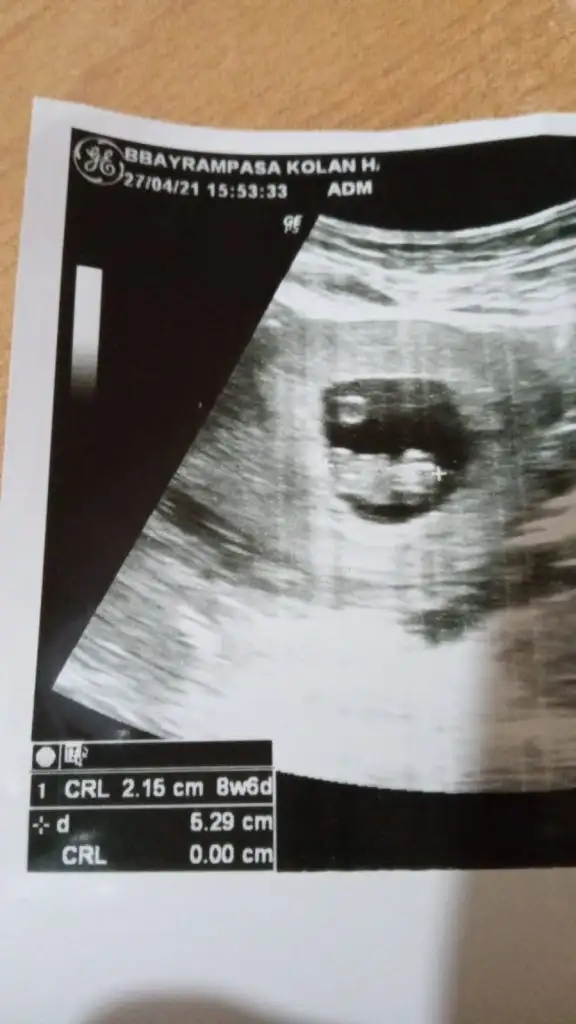

Banada bakarmisiniz

Eklentiler

• IMG-20210427-WA0184.webp

IMG-20210427-WA0184.webp

21,5 KB · Görüntüleme: 60

• IMG-20210427-WA0181.webp

IMG-20210427-WA0181.webp

23,4 KB · Görüntüleme: 56